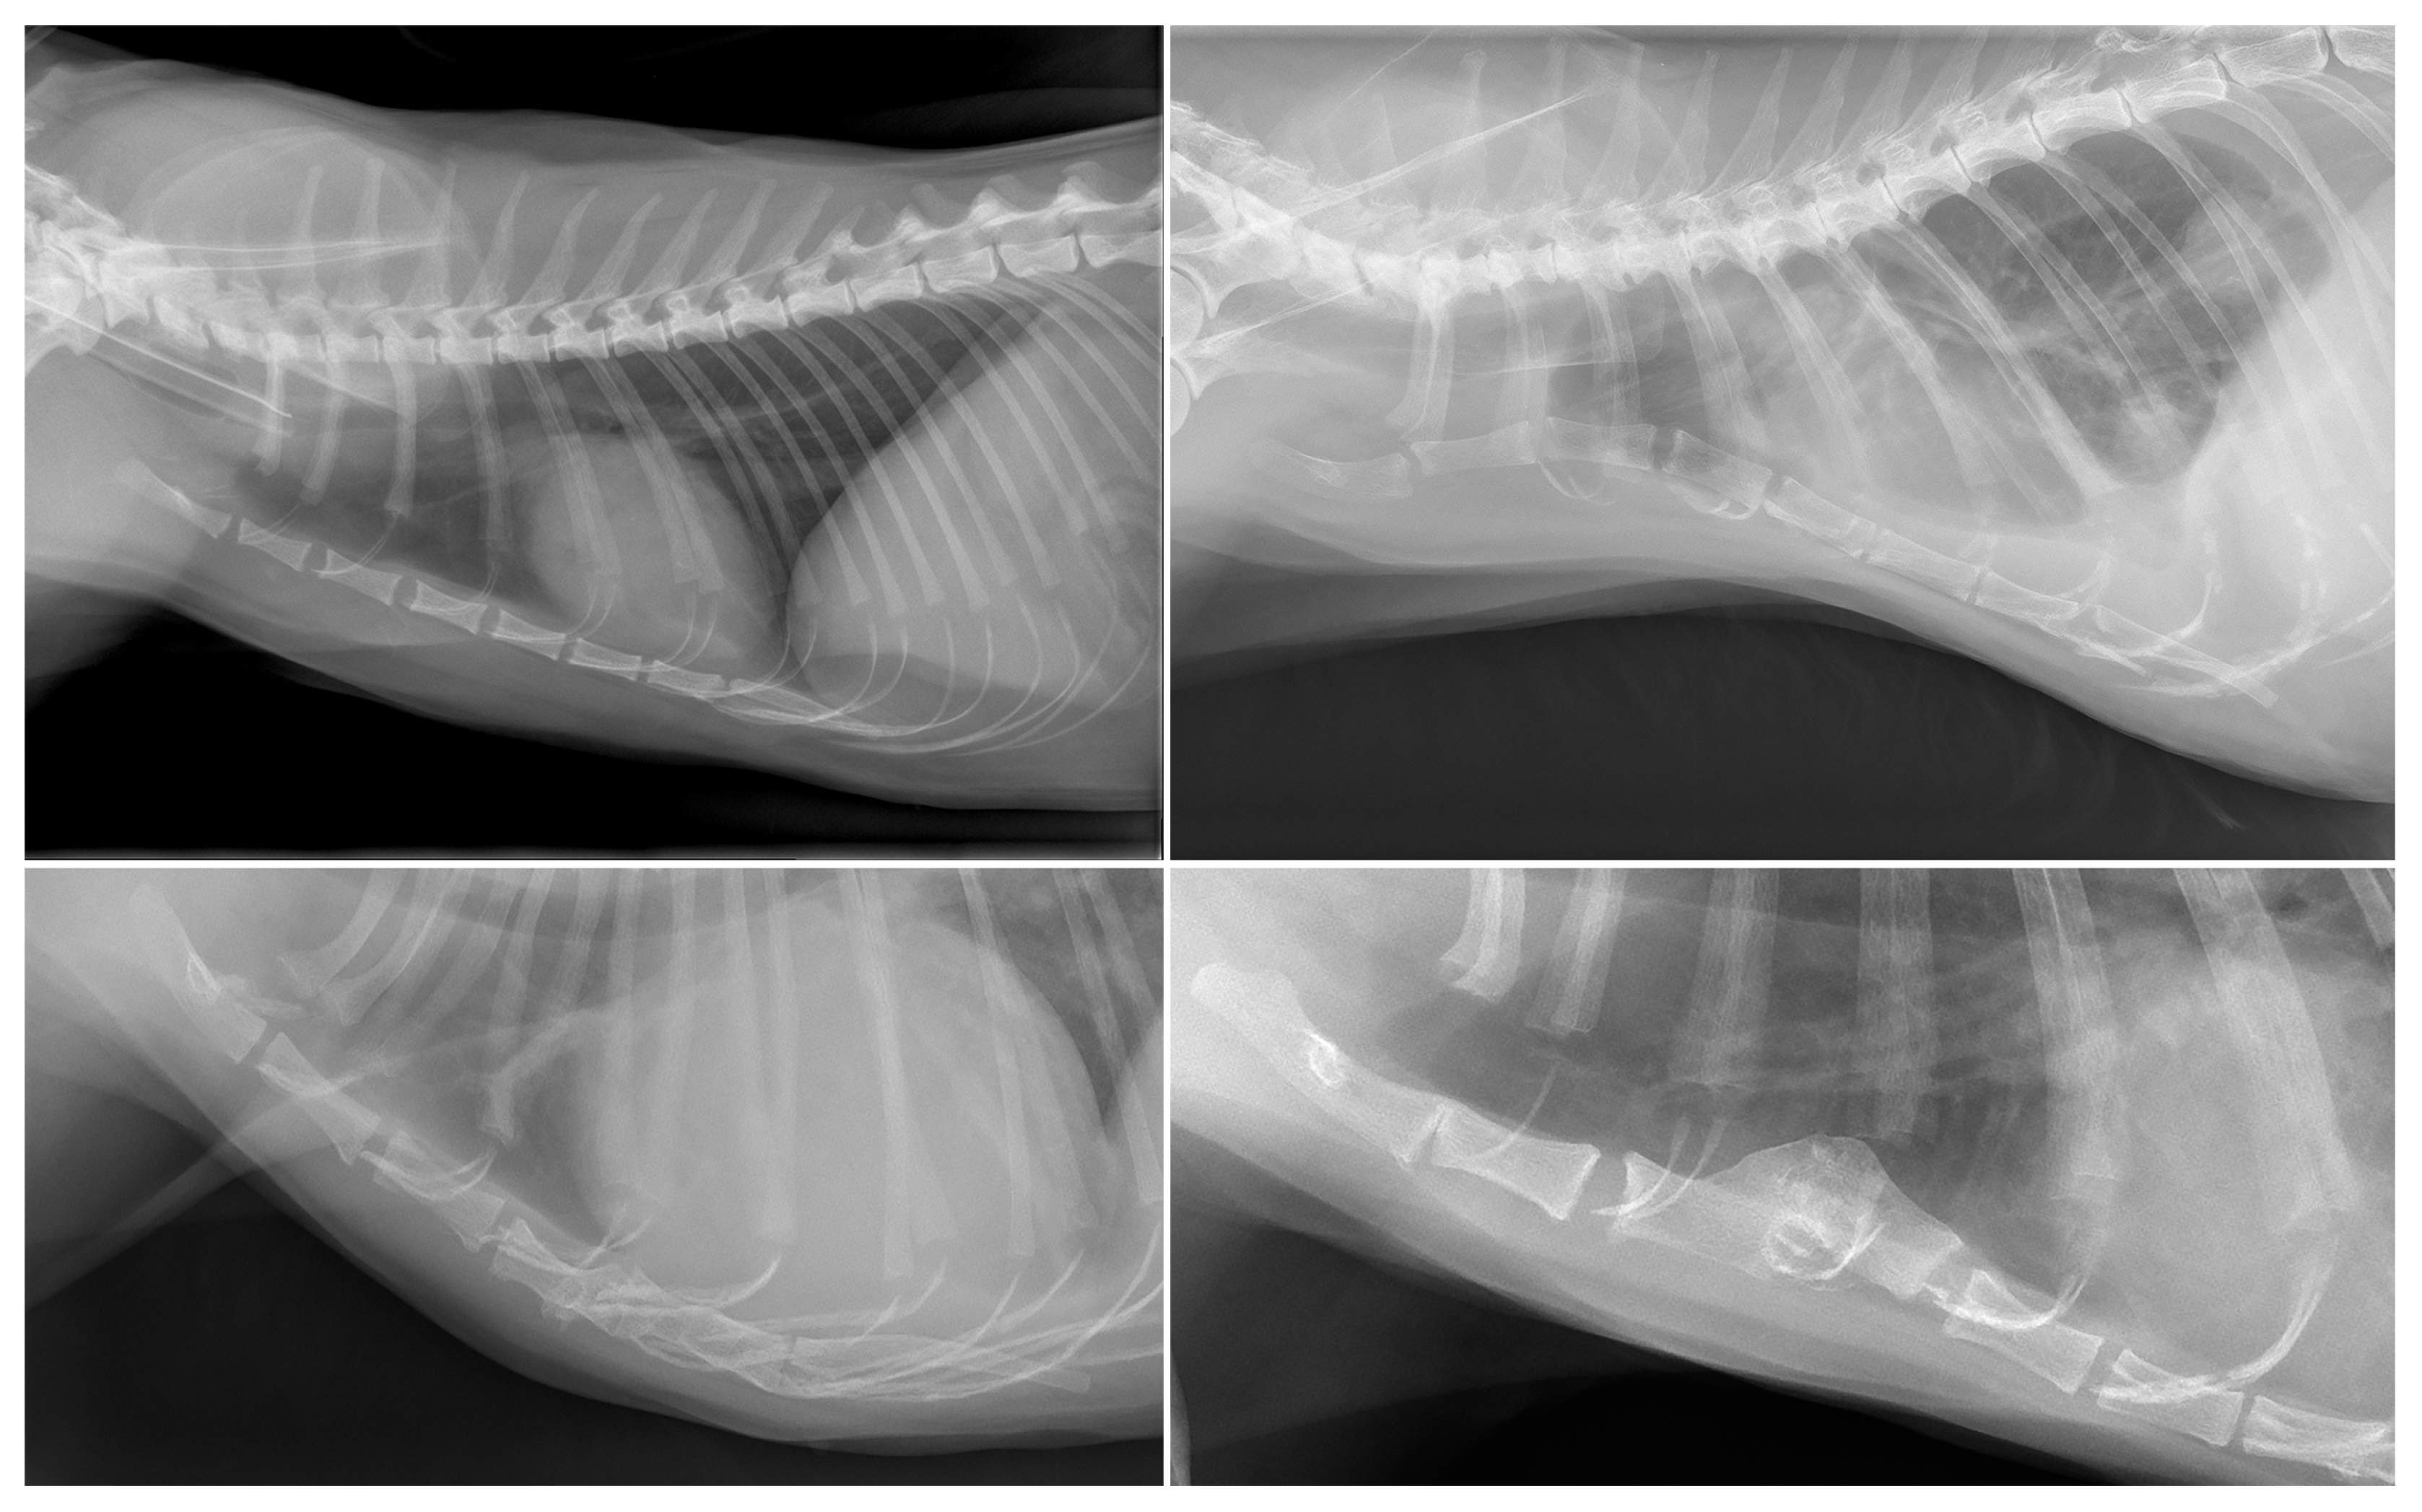

3.1. Dogs

3.2. Cats

| Degeneration (n = 98) | New bone formation (n = 98); collapse (n = 13); vacuum phenomenon (n = 13); sclerosis (n = 9); dislocation (n = 5) | Labrador Retriever (16/62); mixed (13/145); Boxer (7/13); Flatcoated Retriever (7/15); Cavalier King Charles Spaniel (5/11); German Shepherd (5/21); Bernese Mountain Dog (4/26); Belgian Shepherd (3/8); Dachshund (3/19); English Cocker Spaniel (3/13); American Bulldog (2/6); Drentsche Patrijshond (2/6); Golden Retriever (2/23); Irish Setter (2/3); Labradoodle (2/22); Welsh Springer Spaniel (2/3); White Swiss Shepherd Dog (2/14); Anatolian Shepherd Dog (1/1); Border Collie (1/10); Border Terrier (1/4); Bouvier des Flandres (1/2); Chow Chow (1/3); English Springer Spaniel (1/4); Frisian Water Dog (1/2); Hovawart (1/2); Irish Wolfhound (1/2); Jack Russell Terrier (1/15); Kooikerhondje (1/5); Newfoundland (1/5); Dobermann (1/2); Rottweiler (1/10); Spanish Water Dog (1/3); Stabyhoun (1/12); West Highland White Terrier (1/3); Wirehaired Pointing Griffon (1/1) |

| Abnormal number (n = 62) | 9 sternebrae (n = 16) | Labrador Retriever (7/62); Dachshund (2/19); Beagle (1/7); Australian shepherd (1/4); English Cocker Spaniel (1/13); Irish Wolfhound (1/2); mixed (1/145); Rhodesian Ridgeback (1/9); Whippet (1/5) |

| <8 sternebrae (n = 46) | Mixed (10/145); Chihuahua (6/28); Pomeranian (5/14); Labrador Retriever (4/62); Pug (4/7); French Bulldog (3/23); Staffordshire Bull Terrier (2/10); West Highland White Terrier (2/3); American Staffordshire Terrier (1/8); Australian Shepherd (1/4); Bearded Collie (1/2); Boxer (1/13); Drentsche Patrijshond (1/6); Great Dane (1/2); Miniature Pinscher (1/1); Dobermann (1/2); Shih Tzu (1/6); Spanish Water dog (1/3) | |

| Intersternebral cartilage (n = 15) | New bone formation (n = 15); sclerosis (n = 5) | Domestic Shorthair (10/112); Bengal (1/3); British Shorthair (1/10); mixed (1/11); Norwegian Forest (1/4); Siamese (1/4) |

| Abnormal number (n = 27) | 9 sternebrae (n = 7) | Domestic Shorthair (4/112); Bengal (1/3); mixed (1/11); Siamese (1/4) |

| < 8 sternebrae (n = 20) | Domestic Shorthair (13/112); British Shorthair (2/10); Ragdoll (2/7); Oriental Shorthair (1/1); Persian (1/1); Sphynx (1/2) | |

| Post-trauma (n = 3) | Dislocation (n = 3) | Domestic Shorthair (3/112) |